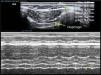

Diaphragm ExcursionTo evaluate diaphragm motion, a 3.5–5MHz probe must be positioned below the rib cage at the level of the mid-clavicular line, directing the ultrasound beam perpendicularly toward the posterior third of the hemidiaphragm. During inhalation, the normal diaphragm moves down, and thus approaches the transducer (Fig. 1).

Normal values in healthy non-ventilated patients differ between men and women (18±3 and 16±3mm, respectively),69 similarly to baseline values in mechanically ventilated patients.71 Diaphragm dysfunction is defined as an excursion of less than 10mm or a negative excursion (or paradoxical movement). These values are also good predictors of failure to wean.72